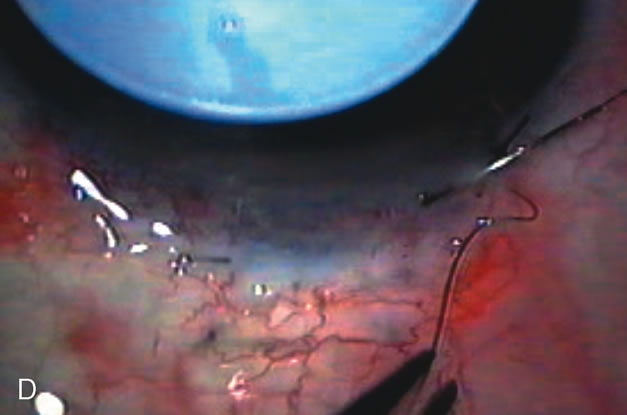

Fig. 7. Phacotrabeculectomy adjacent to a failed filter in cataractous eye. The ability to combine small-incision cataract extraction with trabeculectomy all through the same incision adjacent to the failed filter allows the surgeon to work in a familiar superior area. Avoiding incisions into the existing bleb decreases conjunctival buttonholes, hypotony, operating room time, and subconjunctival bleeding. A. Appearance of failed bleb with exposure of superior temporal quadrant gained with a corneal traction suture. B. Prepare a limbus-based conjunctival flap and a scleral flap. C. This bleb is at high risk to fail again justifying the need for MMC, 0.2 mg/cc applied on a pledget for 4 minutes. D. Insert the keratome and perform phacotrabeculectomy in the usual fashion.